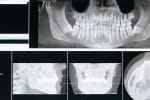

- Radiografii digitale – detectăm problemele ascunse

- Radiografie (dacă e nevoie)